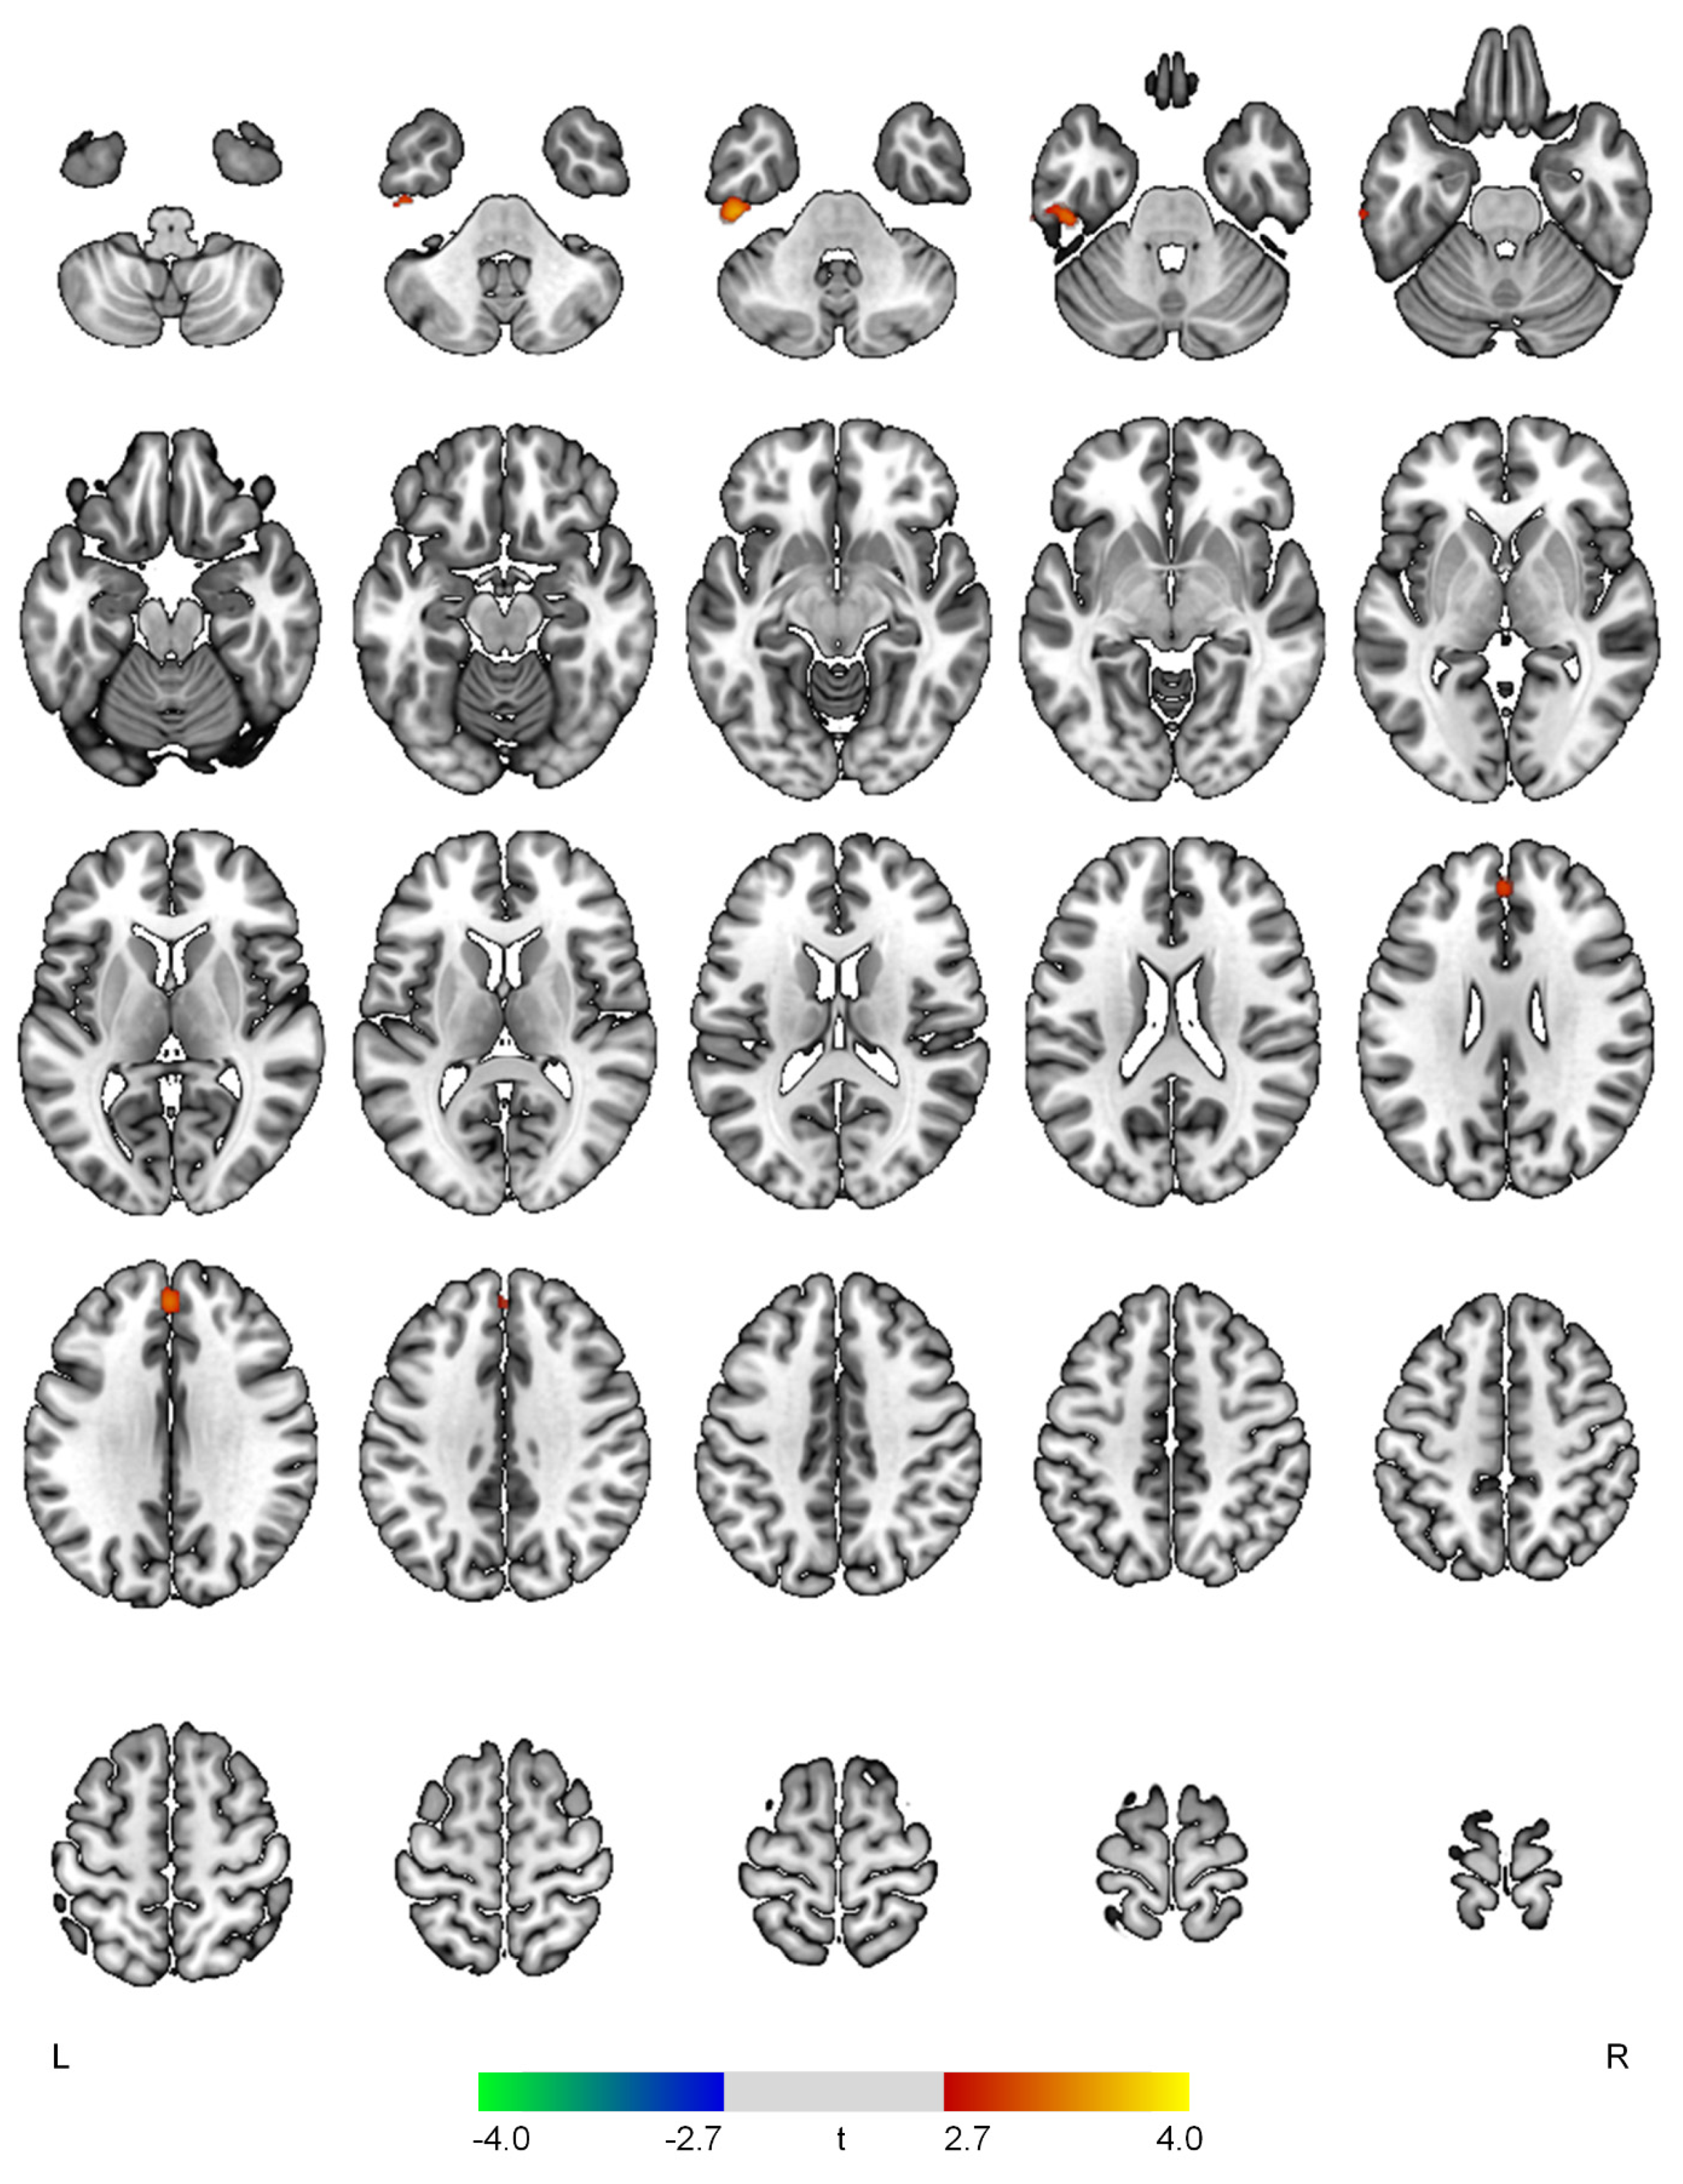

| Positive correlations with the hyperactivity domain | ||||

| L inferior temporal gyrus | 3.66 | <0.001 | 315 | −46, −26, −36 |

| Superior frontal gyrus | 3.30 | 0.001 | 171 | 0, 46, 32 |

| Negative correlations with the hyperactivity domain | ||||

| None | ||||